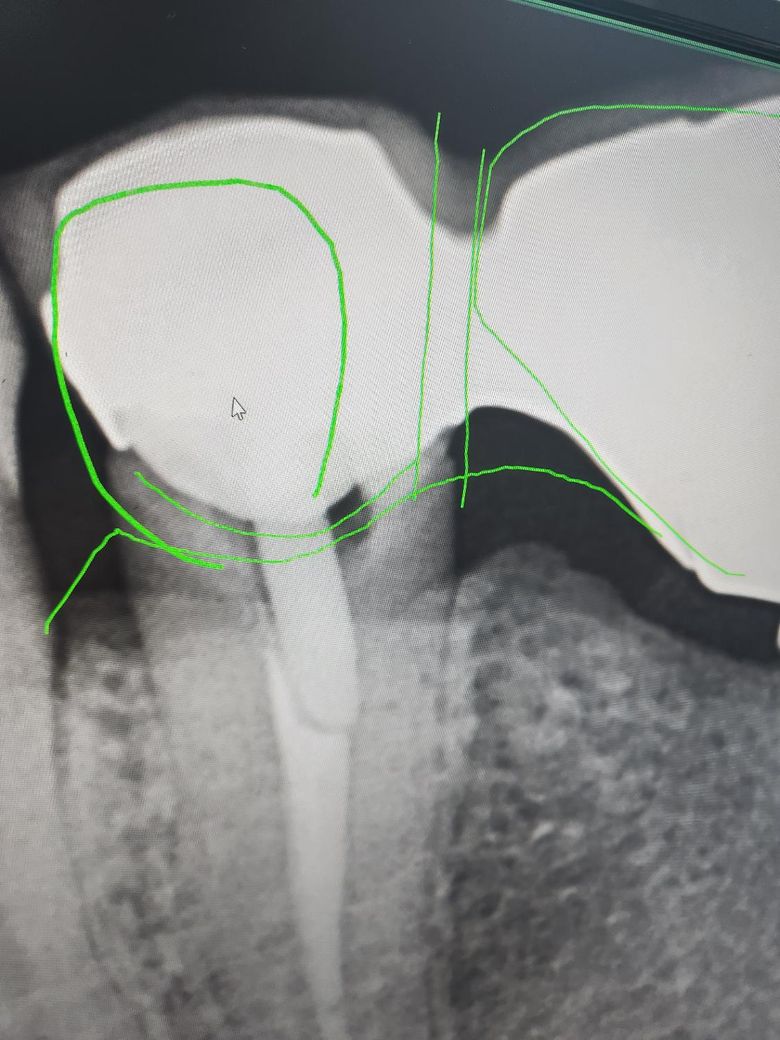

보존과 치과 선생님 계실까요~? 제가 신경치료후 크라운 해놓은 치아가 있는데, 크라운이 치아를 덜 덮어서 밑둥에 충치가 있다고 하던데, 치료가 필요한 치아일까요~? 치료 안하고 양치만 잘해서는 안되는 치아인지 여쭤봅니다. 통증은 전혀 없습니다. ㅠㅠ

• 1번 째 사진

신경치료가 되어 잇어서 통증은 없을꺼에요. 엑스레이 상으로 방사선 투과상이 보이긴 하지만, 통증이 없다면 일단은 관리하시면서 사용해보시는게 좋을것같습니다.

gap이 있어서 이차충치가 그동안 생겼을 가능성이 높은 조건이긴 합니다 신경치료 해놔서 당연히 충치 생겨도 별다른 증상은 없을 수도 있죠 엑스레이찍고 직접 치아 상태 본 치과의사가 뜯고 새로 하자고 했다면 그냥 둬서 좋을게 없는 상황인겁니다